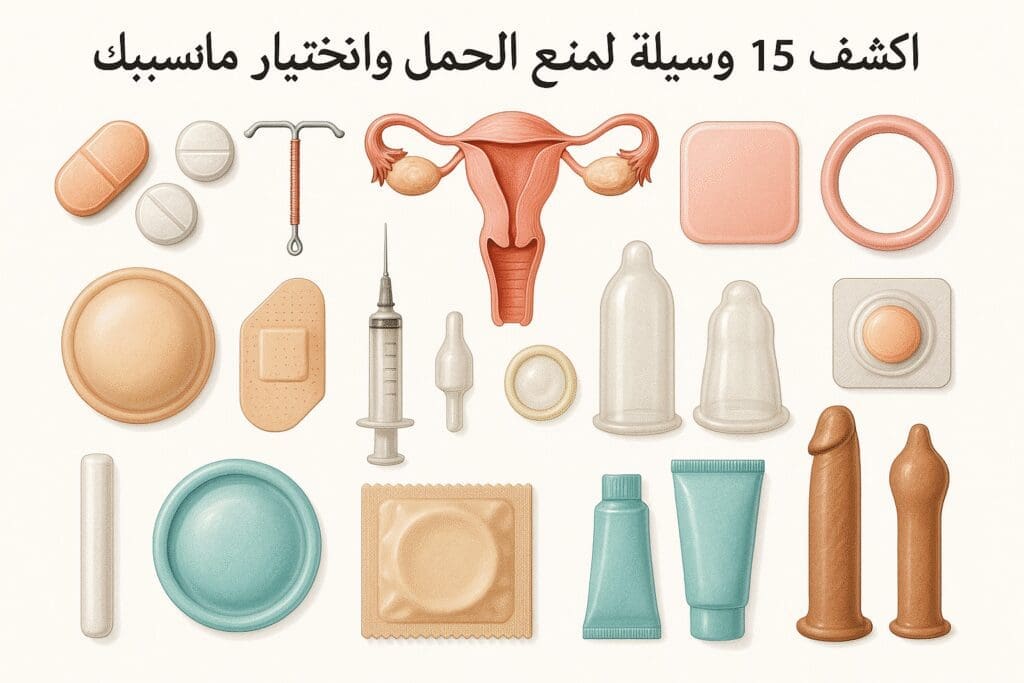

مقالات طبية من مساهمات الأطباء